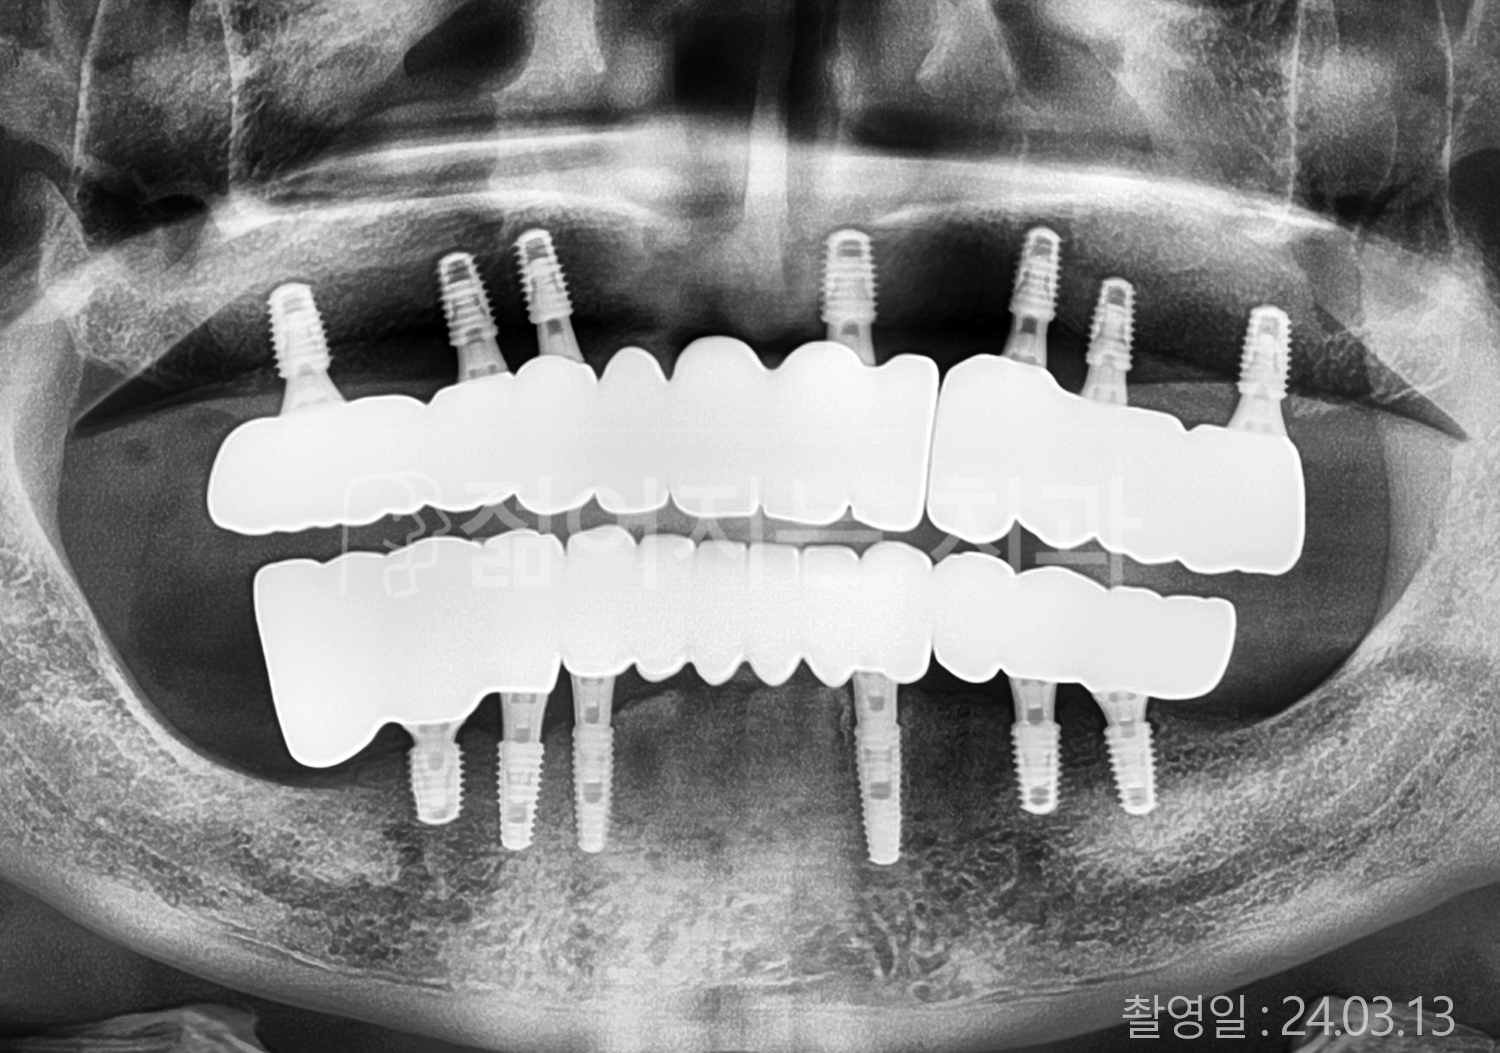

• 60대 고혈압, 고지혈증 전체치아 10개 이상 임플란트

• 70대 전체치아 10개 이상 임플란트

• 60대 전체치아 10개 이상 임플란트

• 50대 전체치아 10개 이상 임플란트

• 50대 고혈압, 고지혈증 전체치아 10개 이상 임플란트

• 60대 고혈압, 당뇨, 고지혈증 전체치아 10개 이상 임플란트

• 80대 고혈압, 당뇨, 골다공증 전체치아 10개 이상 임플란트

• 60대 고혈압 전체치아 10개 이상 임플란트

• 60대 고지혈증 전체치아 10개 이상 임플란트

• 60대 당뇨 전체치아 10개 이상 임플란트